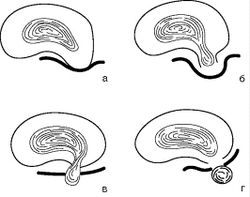

К дистрофическим изменениям позвоночника, определяемым при МРТ, относят снижение интенсивности сигнала от дисков, их выпячивание, формирование протрузий, экструзий и секвестрация, складчатость фиброзного кольца, изменение сигнала от концевых пластинок, «вакуум-феномен», стеноз канала. Под выпячиванием диска понимают циркулярное, симметричное выбухание фиброзного кольца диска за пределы замыкательных пластинок тел прилежащих позвонков. Термин «протрузия» (грыжа пульпозного ядра, пролапс) означает истончение фиброзного кольца с фокальным пролабированием пульпозного ядра за края замыкательных пластинок тел прилежащих позвонков. При протрузии не нарушается целостность задней продольной связки и сохраняются самые наружные волокна фиброзного кольца. Экструзия - пролабирование пульпозного ядра за пределы фиброзного кольца, при этом часть диска, подвергшаяся экструзии, связана с оставшимся пульпозным ядром тонкой ножкой (рис. 12). Протрузии и экструзии по направлению их пролабирования условно подразделяют на передние (расположенные по передней полуокружности тел позвонков, не имеющие большого клинического значения) и задние. Последние можно разделить на латеральные (направленные в сторону межпозвоночного отверстия), парамедианные и срединные (рис. 13). Секвестрация - термин, применяющийся для обозначения формирования свободного фрагмента, полностью утратившего связь с диском.